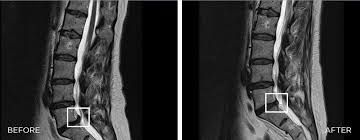

Lassen Sie die Bilder auf sich wirken - auch beim MRT ist zu erkennen dass sich ein Bandscheibenvorfall nach mehreren Sitzungen

deutlich zurückbilden kann!